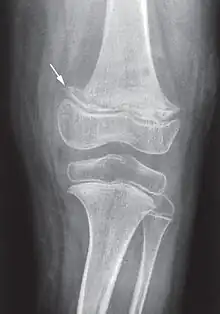

It takes at least a month of little to no vitamin C in the diet before symptoms occur.[1][2] In modern times, scurvy occurs most commonly in people with mental disorders, unusual eating habits, alcoholism, and older people who live alone.[2] Other risk factors include intestinal malabsorption and dialysis.[2] While many animals produce their own vitamin C, humans and a few others do not.[2] Vitamin C is required to make the building blocks for collagen.[2] Diagnosis is typically based on physical signs, X-rays, and improvement after treatment.[2]

Diagnosis is typically based on physical signs, X-rays, and improvement after treatment.[2]